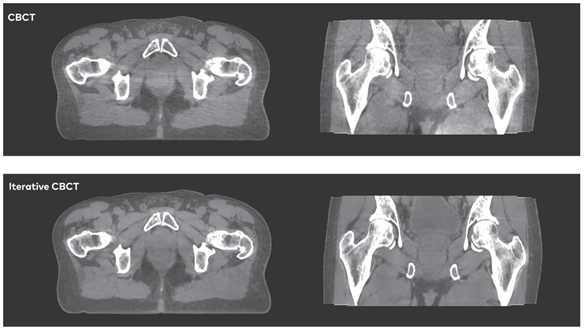

“精确瞄准,定点打击”一直是放射治疗的理念和目标。新一代速锐2.0加速器引入的千伏级成像系统和高质量iCBCT图像重建模式,可提供诊断CT级的高清图像,以此为基础的图像引导治疗(image-guided radiotherapy,IGRT)模式,可以将自适应放疗精度提升到历史性的新高度,保障患者得到最精确的放射治疗。

媲美诊断CT级的盆腔iCBCT ,保证肿瘤看得清,打得准